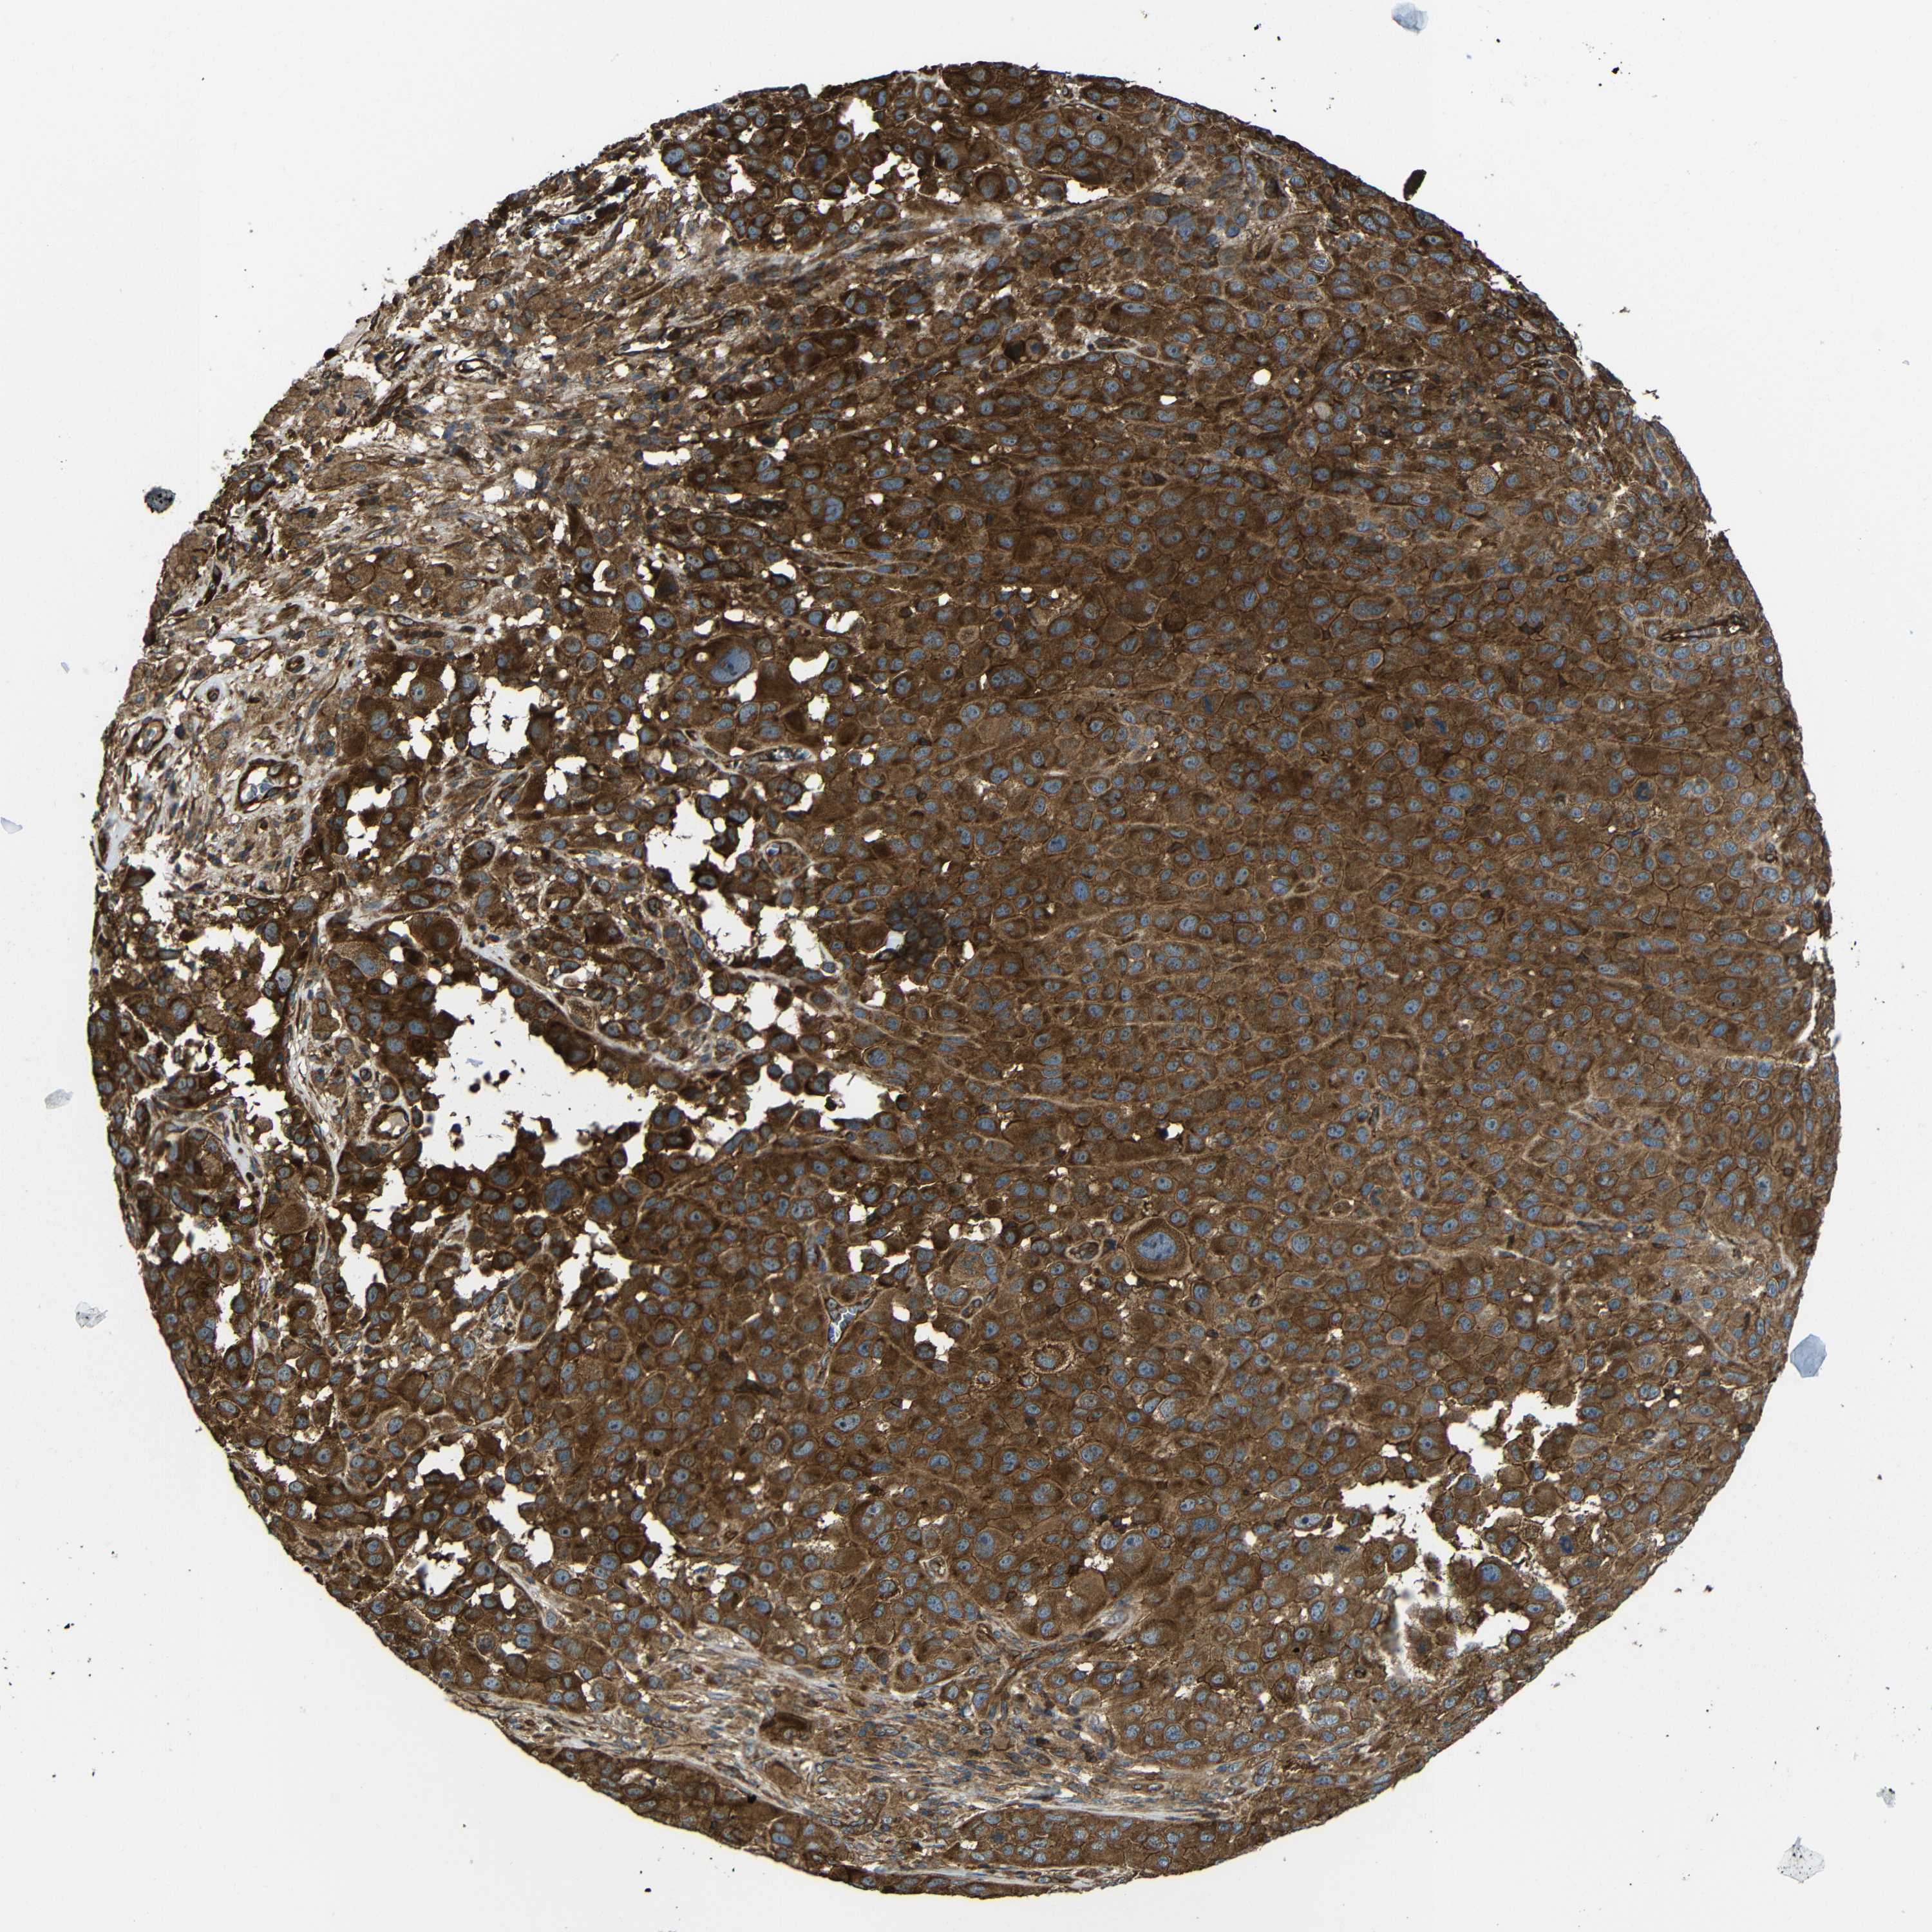

MELANOMA - Protein expressioni

A mouse-over function shows sample information and annotation data. Click on an image to view it in a full screen mode. Samples can be filtered based on level of antibody staining by selecting one or several of the following categories: high, medium, low and not detected. The assay and annotation is described here.

Note that samples used for immunohistochemistry by the Human Protein Atlas do not correspond to samples in the TCGA dataset.

Antibody stainingi

Antibody staining in the annotated cell types in the current human tissue is reported as not detected, low, medium, or high, based on conventional immunohistochemistry profiling in selected tissues. This score is based on the combination of the staining intensity and fraction of stained cells.

Each image is clickable and will lead to virtual microscopy that enables deeper exploration of all samples and also displays staining intensity scores, fraction scores and subcellular localization as well as patient and tissue information for each sample.

Antibody CAB013717

Staining

High

Medium

Low

Not detected

Intensity

Strong

Moderate

Weak

Negative

Quantity

>75%

75%-25%

<25%

None

Location

Nuclear

Cytoplasmic/membranous

Cytoplasmic/membranous,nuclear

Malignant melanoma, NOS

Malignant melanoma, Metastatic site